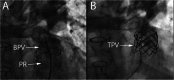

There is a growing appreciation for the adverse long-term impact of right-sided valvular dysfunction in patients with congenital heart disease. Although right-sided valvular stenosis and/or regurgitation is often better tolerated than left-sided valvular dysfunction in the short and intermediate term, the long-term consequences are numerous and include, but are not limited to, arrhythmias, heart failure, and multi-organ dysfunction. Surgical right-sided valve interventions have been performed for many decades, but the comorbidities associated with multiple surgeries are a concern. Transcatheter right-sided valve replacement is safe and effective and is being performed at an increasing number of centers around the world. It offers an alternative to traditional surgical techniques and may potentially alter the decision making process whereby valvular replacement is performed prior to the development of long-term sequelae of right-sided valvular dysfunction.